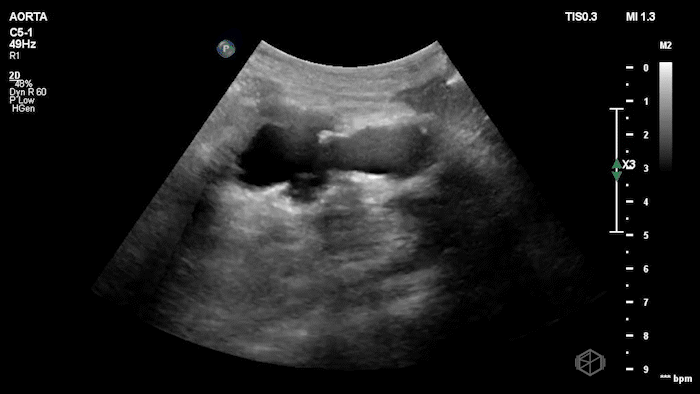

Dr. Flouskakos is on the US rotation currently and was scanning a late 80’s female with mild left lower quadrant and left flank pain when he noticed the following findings:

Upon scanning the aorta, it was noted that the patient an enlarged infra-renal abdominal aorta with an eccentric left thrombus, measuring approximately 4.05cm consistent with an abdominal aortic aneurysm. On lateral view the aneurysm appears more saccular than fusiform. CT was done which confirmed the finding: Saccular infrarenal abdominal aortic aneurysm with partially thrombosed aneurysm sac eccentric to the left measuring up to 4.0 cm.

Diagnosis: Saccular aortic aneurysm